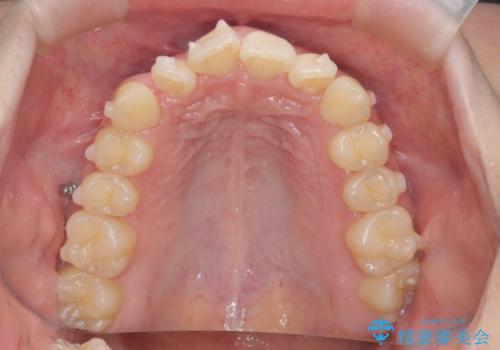

- 前歯のねじれを主訴に来院。

前から2番目の歯がねじれて下の歯の内側に入っていました。

また、奥歯のかみ合わせが上の奥歯が若干前に並んでおり、それで前歯が入りきらずにねじれていました。

歯を抜かずに奥歯を後ろに下げてマウスピースで矯正しています。

上の奥歯を後ろに下げて前歯のねじれを治すスペースを確保しました。

奥歯を後ろに下げるために、矯正用インプラントを使用しています。